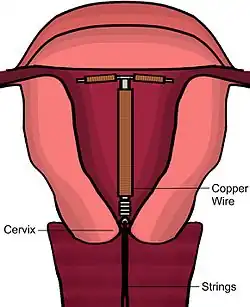

Device description

There are various of models of copper IUDs available around the world. Most copper devices consist of a plastic (polyethylene) core that is wrapped in a copper wire.[10] Many of the devices have a T-shape similar to the hormonal IUD. However, there are "frameless" copper IUDs available as well, the most popular of which is marketed as GyneFix. Early copper IUDs had copper around only the vertical stem, but more recent models have copper sleeves wrapped around the horizontal arms as well, increasing copper surface area and thereby effectiveness.[37][38]

Mechanism of action

The copper IUD's primary mechanism of action is to prevent fertilization.[11][21][43][44][45] Copper causes a localized inflammatory response, which is spermicidal and causes the endometrium to be inhospitable.[11][21][16][43]

Spermatozoa entering the uterine cavity and cervical mucus are consumed by local phagocytes, and are also directly killed by copper ions and lysosome contents. Presence of copper ions disrupts sperm motility, rendering fertilization improbable.[1]

Although not a primary mechanism of action, copper may disrupt embryonic implantation,[11][46] especially when used for emergency contraception.[47][48] However, if implantation occurs, there is no evidence that copper affects subsequent development of a pregnancy or causes embryonic failure.[11][43] Therefore, the copper IUD is considered to be a true contraceptive and not an abortifacient.[11][21]